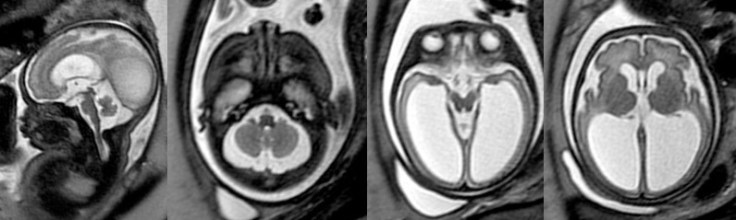

sténose de l’aqueduc associée à une malformation du cervelet (rhombencephalosynapsis) - des possibles malformations cérébrales associées, pas forcément visibles sur l’imagerie

il s’agit d’une hydrocéphalie obstructive, liée à une lésion malformative, cicatricielle ou tumorale de l’aqueduc de Sylvius, un passage obligé pour le liquide cérébro-spinal (LCS) ; cette hydrocéphalie est souvent mal tolérée cliniquement du fait d’un gradient de pression entre différentes régions du cerveau. Le traitement de choix est la ventriculo-cisternosomie endoscopique, qui permet de rediriger le LCS vers les espaces méningés, mais ce traitement est souvent inefficace chez les petits nourrissons

c’est une hydrocéphalie obstructive, souvent mal tolérée cliniquement, mais évoluant parfois de façon chronique.